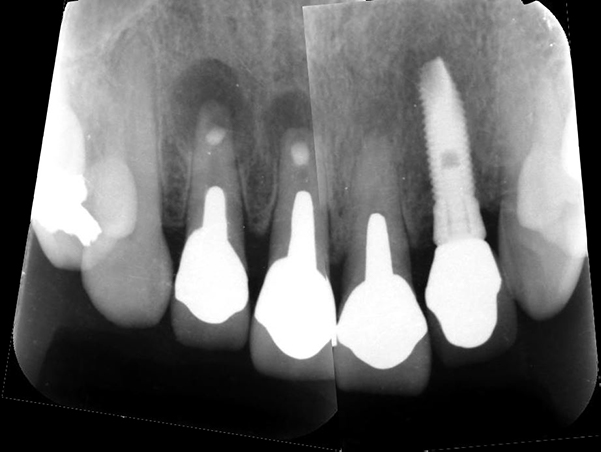

CTによる診査

CTを撮影し、歯根の長さや根尖病変の大きさを精査しました。

診断

2 1|1 根尖性歯周炎

2 1|→保存を試みるならば再歯根端切除術を行うことになるが、健全歯質が少なく、また根が短くなり歯の揺れが悪化することから保存不可と判定しました。 |1→RCTにて保存は可能であるが、失活歯のため将来的に歯根破折のリスクが高いことが予想されました。